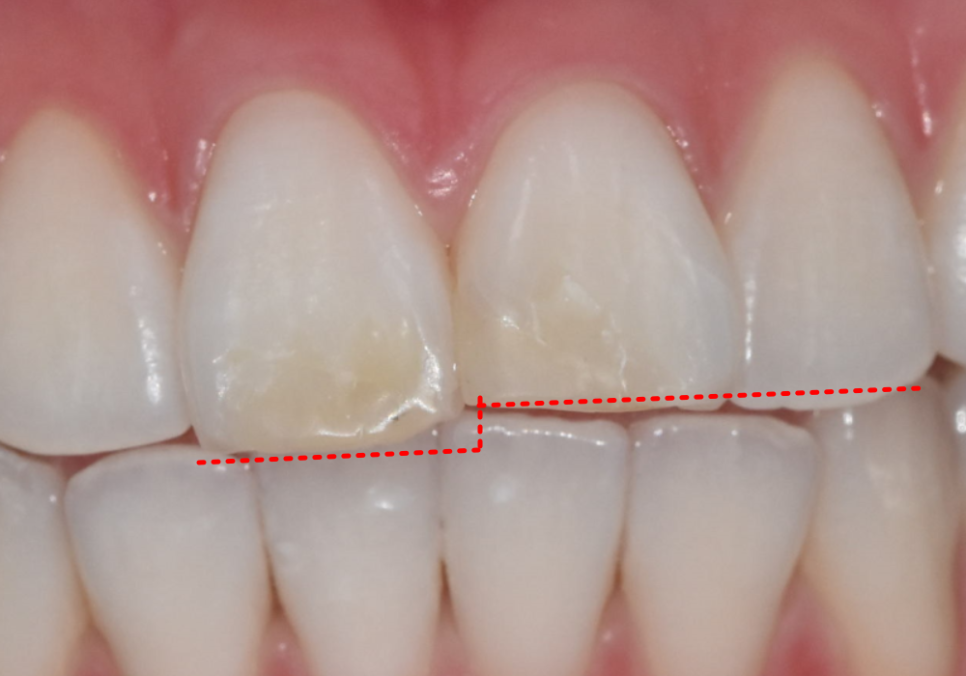

오늘 소개할 환자분도

어릴 때부터 절단교합을 갖고 계셨습니다.

한 번 앞니가 깨진 뒤 레진으로 여러 번 수복했지만

씹을 때마다 같은 자리에 힘이 실리면서

또 깨지고, 또 변색되는 상황이 반복됐습니다.

250203

최근에는 레진이 다시 깨지면서

오른쪽과 왼쪽 앞니 길이가 다르게 보이고

앞니가 살짝 앞으로 뻗어 보이는 돌출감도 겹쳐

웃을 때마다 더 신경 쓰인다며 내원하셨습니다.